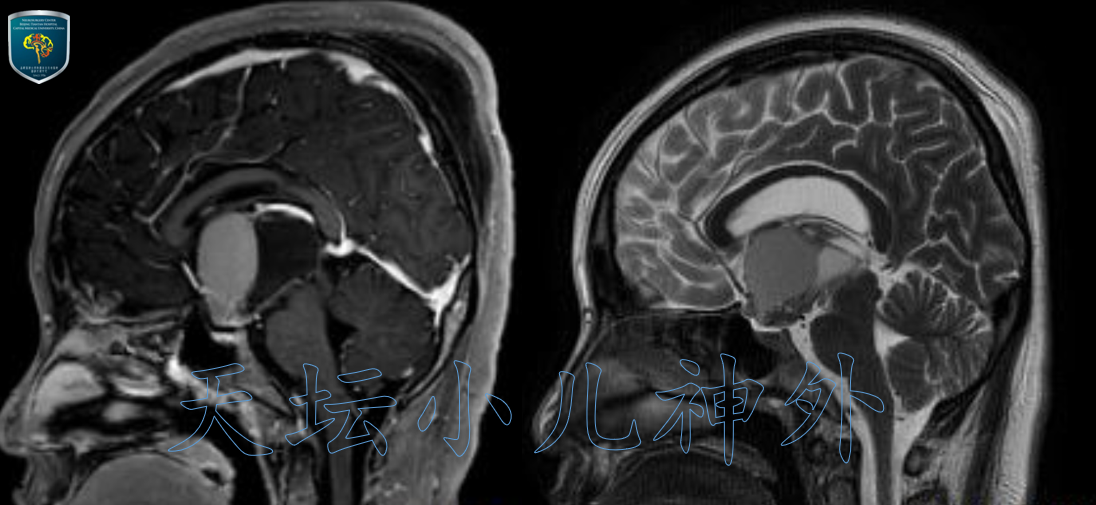

2020年11月接诊一例来自山东莒县12岁女性患儿(158cm,52.0kg),主诉:间断头痛1月,双眼视力下降5天。当地医院检查示巨大鞍区占位,遂来我院就诊。门诊查体示:神清语利,自主体位,双眼视力下降,眼前20cm数指,双瞳等大、光反应灵敏,余神经系统查体阴性。术前激素水平正常;头颅CT平扫显示:鞍区囊实性占位伴钙化,梗阻性脑积水伴室旁水肿,颅咽管瘤?(图1)。MRI显示:蝶鞍扩大,鞍上囊实性占位突入第三脑室,视交叉受压,长圆形混杂信号影,边界清晰,大小约40*25*25mm,囊壁不均匀强化,颅咽管瘤可能性大(图2)。